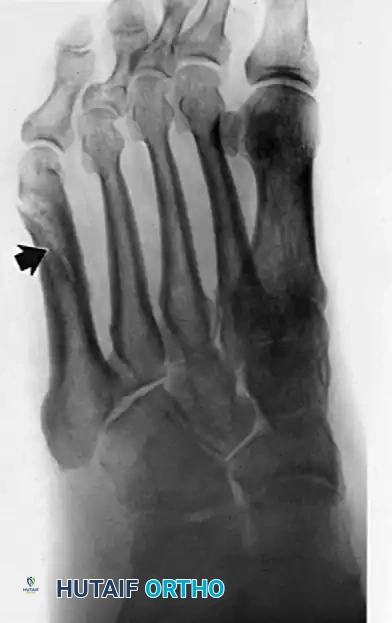

- Plain Radiographs: Weight-bearing anteroposterior, lateral, and mortise views of the ankle and foot are obtained to rule out fractures (e.g., "fleck sign" indicating SPR avulsion), os peroneum pathology, or varus hindfoot alignment.

Radiographic evaluation of the foot and lateral column.